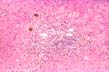

Fig.136-TB granuloma

,early, in the middle of the lobule. On the part of the liver there is only moderate, non-specific portal inflammation and some compression of the liver plates.(H&E stain)

Same TB granuloma

Fig.137-Same TB granuloma

at higher power containing histiocytes and many neutrophils which are a distinguishing feature from non- infectious granulomas. No giant cells nor caseation necrosis at this early stage.(H&E).